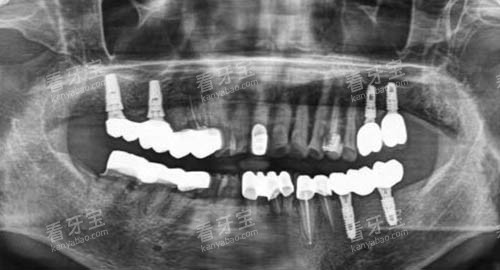

患者初次到店时,医护人员会新型行详细的口腔检查,包括口腔CT、全景片、牙周探诊等,多方面掌握牙齿、牙龈、牙槽骨的健康状况。

例如,针对种植牙患者,医生会通过3D导板技术更准一些定位种植体位置,避免盲目操作;针对正畸患者,则会通过智能化扫描生成牙齿模型,提前模拟矫正结果,让患者直观了解治疗过程。

此外,机构引入智能化诊疗设备,如CBCT三维成像、口腔扫描仪、种植导航系统等,通过技术手段提升操作更准一些度,减少人为误差。